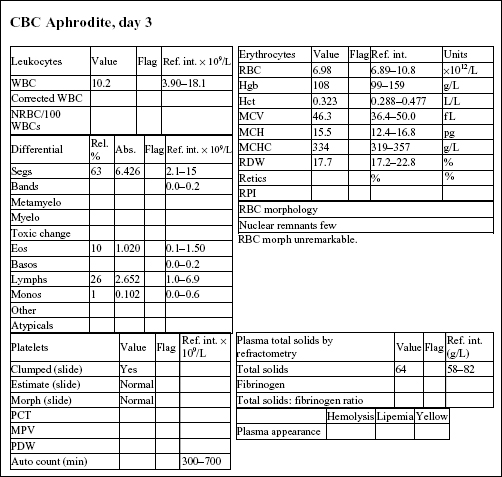

The CBC from day 3 is within reference limits. The absolute erythrocytosis and the inflammation were corrected with conservative therapy. Although a foreign body was suspected initially, Aphrodite recovered completely without surgical intervention.